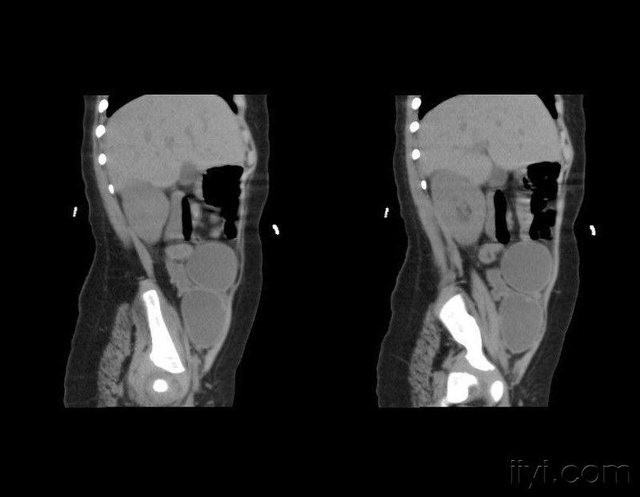

内分泌专家让女子先去做个血液检查,然后做一个腹部B超再来找他。

性别出现问题,女儿身变男生过了没多久,女子就带着检查报告回来了,内分泌专家一看血检报告,好家伙她的血钾竟然只有2.28mmol/L,血液却有180/110mmHg,于是专家问:“你平时会不会感觉头晕脑胀不舒服”?

然后医生又看了看女子的腹部B超,显示子宫和卵巢存在着明显问题,看到这时,内分泌科专家心中基本已经有了答案,这是很典型的先天性肾上腺皮质增生症,但是眼前的证据暂时还不足以支撑诊断,于是专家又让她去做个肾上腺CT。结果出来后果然和专家预估的一模一样。